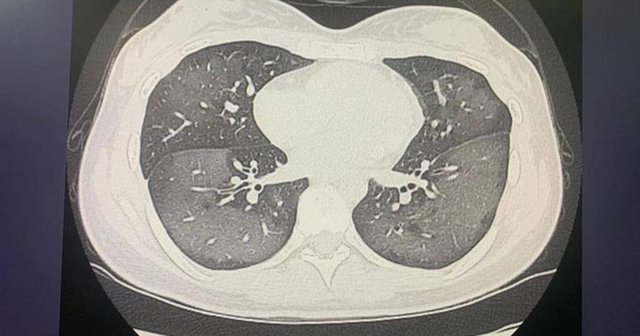

3 thói quen sử dụng điều hòa phá chức năng phổi cực mạnh, nhiều người mắc phải mỗi ngày- Ảnh 1.